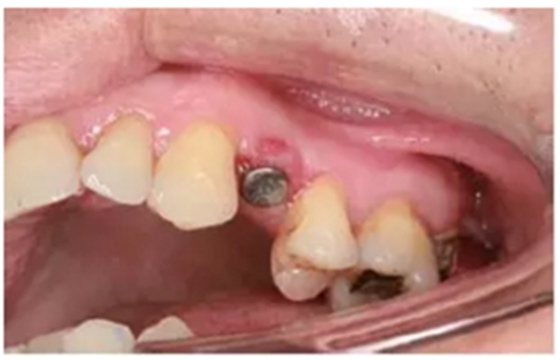

種植手術(shù)完成2周后進(jìn)行拆線??梢钥闯鲕浗M織愈合良好。

圖8 拆線時(shí)的口內(nèi)照片